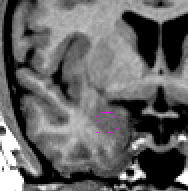

|  | Drawing lines around the amygdala in the axial view (particularly inferiorly) and sagittal (also inferiorly) will help with the shape of the anterior amygdala in the coronal view.

| Part III - Hippocampus appears When the ILV is first visible, it is likely that the hippocampus is present; check for your hippocampal sulci lines as well. To segment the amygdala in this area, use a contour line to define the hip-amyg area. Call up your sulci lines. Depending on the brain, you will see darker pixels that represent the ILV, or lighter pixels that represent the fimbria of the hippocampus (or both) along your sulci lines. If possible, draw a line separating the amygdala from the hippocampus along the dark pixels of ILV. Try increasing the contrast between black and white to better see this division. If after manipulating the brightness/contrast this line is not visible, draw a line that bisects your sulci lines. Then use projection lines to verify that your line really is the division between the hippocampus and the amygdala. When you are satisfied, unextract the hip-amyg outline, and extract the top portion as amygdala. | |